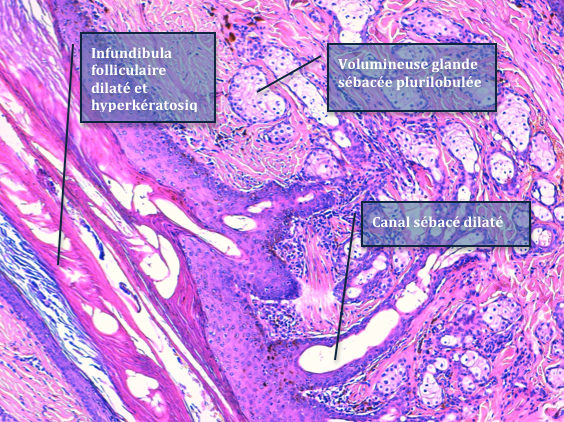

La plupart révèlent un épiderme hyperplasique auquel s’abouchent des infundibula folliculaires évasés, hyperkératosiques, auxquels sont annexées de nombreuses glandes sébacées, plurilobulées, hyperplasiques, via des canaux sébacés dilatés et multiples. Au sein des unités folliculaires, les follicules pileux montrent une portion profonde rudimentaire souvent sous la forme d’un bulbe isolé et malformé. Les glandes sudorales épitrichiales sont rares et de petites taille dans le derme profond.

| Fig 3 : Hamartome sébacé de Jadassohn : de multiples glandes sébacées plurilobulées, ramifiées et matures, s’abouchent à un même infundibulum folliculaire béant, via des canaux sébacés (H&E, X 25). | |

| Fig 4 : Hamartome sébacé de Jadassohn : de multiples glandes sébacées plurilobulées, ramifiées et matures, s’abouchent à un même infundibulum folliculaire béant, via des canaux sébacés (H&E, X100) | |